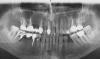

Алин Опубликовано 10 декабря, 2010 Поделиться Опубликовано 10 декабря, 2010 Здравствуйте, уважаемые доктора! Прилагаемый снимок сделан в марте, за 2 дня до удаления отмеченного зуба. Тогда мой доктор сказал, что с остальными зубами проблем нет и надо готовиться к имплантации. В конце октября сделал КТ и справа внизу поставили импланты. Все прошло без осложнений. На прошлой неделе показался доктору и он подтвердил, что с имплантами все нормально, но, посмотрев еще раз КТ, "обрадовал" - состояние верхних 6-к и 7-к критическое и в скором времени их можно лишиться, если сейчас не заняться перелечиванием. Но меня. кроме небольшой припухлости нёба в районе этих зубов, ничего не беспокоит! Пошел в другую клинику на консультацию. Доктор посмотрел КТ и сказал, что серьезных проблем не видит и не рекомендует пока трогать эти зубы. Имею два противоположных мнения. Хочется верить второму доктору, но страшно упустить время, если первый прав... Буду очень благодарен, если поможете принять правильное решение.КТ здесь http://files.mail.ru/80KLKW Ссылка на комментарий

Bier Опубликовано 11 декабря, 2010 Поделиться Опубликовано 11 декабря, 2010 там явно есть кариес под коронками. Неплохо бы сделать ревизию, поставить вкладки и сделать новые коронки. Ссылка на комментарий

Алин Опубликовано 13 декабря, 2010 Автор Поделиться Опубликовано 13 декабря, 2010 там явно есть кариес под коронками. Неплохо бы сделать ревизию, поставить вкладки и сделать новые коронки. Спасибо Bier! Сегодня был еще в одной клинике у эндодонта. Он дал направление на снимок, посмотрел его, посмотрел КТ и сказал, что за эту работу не возьмется, т.к. не видит благоприятного исхода. Опять непонятка... 2 - за спасение, 2 - против... Может кто-нибудь еще выскажет своё мнение? Сегодняшний снимок - http://files.mail.ru/EXPKDN?t=1 Ссылка на комментарий